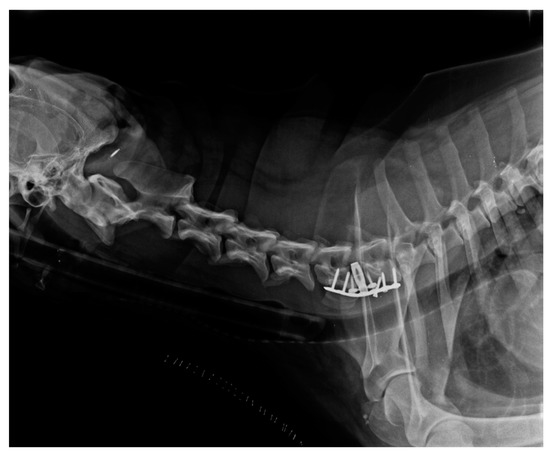

4. Discussion